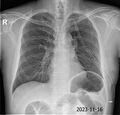

1. X-ray 촬영

1. X-RAY 촬영. 전면 및 측면 두 장

1. 오늘 찍은 X-RAY보면서 괜찮다. 폐렴 없다.